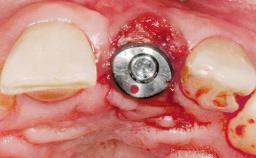

Immediate Flapless Placement of an Implant in a Maxillary Left Central Incisor Site

A 42-year-old female patient was referred to our clinic at the School of Dentistry of the University of São Paulo in November 2004, presenting a deficient restoration in the upper left central incisor. The clinical examination revealed no gingival retraction or any signs of gingival inflammation and, therefore, previous periodontal treatment was not considered. The patient presented a high lip line at full smile and a thin tissue biotype. This combination characterized a high-risk situation from an anatomic point of view, which required careful preoperative planning and cautious surgical execution.

Placement Protocol Immediate implant placement

Socket Morphology Single-root socket

Socket Integrity Sufficient, with intact bone walls